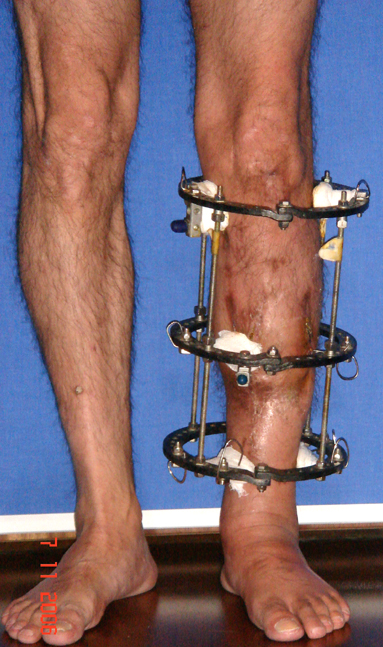

The duration of external fixation (external fixation index) depends on the amount of distraction required, and the extremity is prone to complications during this period. After the distraction phase is completed, the external fixator remains in place during the consolidation phase, which lasts twice as long as the distraction phase; but this period is hardly tolerated. If the external fixator is removed before sufficient consolidation is achieved, fractures, deformity and shortness will be the result. In our department, ‘lenghthening over nail’ method is used in order to decrease the external fixation index and increase patient comfort and activity level. In this method, the intramedullary nail is statically locked after the completion of the distraction phase, and external fixator is removed. The extremity is stabilized by the intramedullary nail during consolidation phase. In this way, complications due to long external fixation index or early removal of the external fixator are avoided.

Case 1